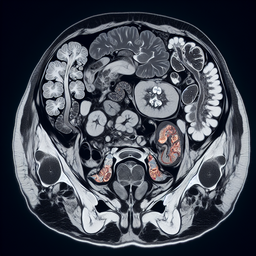

МРТ органів малого тазу

Магнітно-резонансна томографія (МРТ) органів малого тазу — це неінвазивний метод діагностики, що використовує магнітні поля та радіохвилі для отримання детальних зображень внутрішніх структур. Цей метод дозволяє лікарям оцінити стан органів малого тазу, таких як сечовий міхур, простата у чоловіків, матка та яєчники у жінок, а також навколишні тканини й лімфатичні вузли.